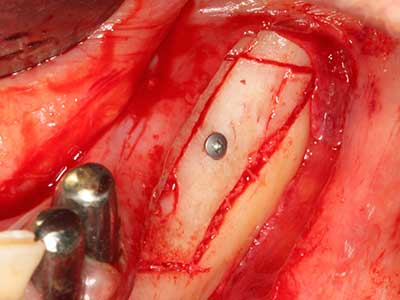

Abb. 18: Präparation eines Kortikalis-Deckels mit der Piezo-Knochensäge (Piezomed, W&H).

Abb. 19: Operationssitus nach Neurolyse und Osteomentfernung.

Abb. 20: Der entnommene Knochendeckel wird readaptiert und durch eine Osteosyntheseschraube (KLS Martin, Tuttlingen) fixiert.